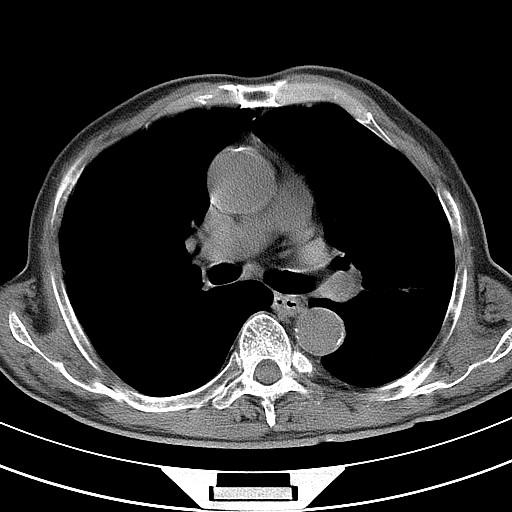

标题: CT18248:男,71岁,糖尿病住院,无发热、咳嗽、咳痰。 [打印本页]

男,71岁,糖尿病住院,无发热、咳嗽、咳痰。

符合双肺继发性结核感染

支持结核,建议痰菌检查;左侧上叶间隔旁型肺气肿

符合双肺继发性结核